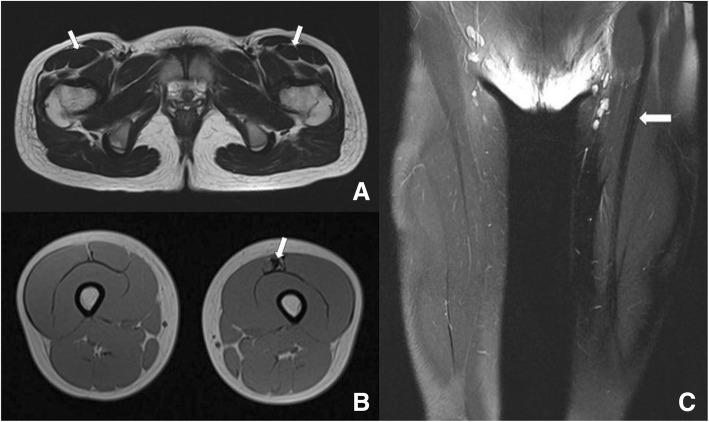

MRI (Fig. 2) indicated that muscle volume of the left RF was smaller than the right one, and dark-signal intensity was detected inside the left RF muscle in transverse T1-weighted and T2-weighted images. By comparison with other muscles in the ipsilateral thigh or contralateral RF, the unnormal signal intensity suggest atrophy of the RF on the affected side. On the coronal sections, a hypointensity band connected the anterior inferior iliac spine with the patella was legible. The imaging findings implied that degeneration occurred in the RF muscle, or the latter was displaced by the fibrosis.

Fig. 2.

Preoperative MRI findings. Transverse T2-weighted image (a) showing volume reduction of left rectus femoris muscle. Transverse T1-weighted image (b) demonstrating fibrosis with dark signal intensity in the anterior of left rectus femoris. A hypointensity band could be observed on the coronal section (c) in the image. White arrow in A: rectus femoris muscle; White arrow in B &C: hypointensity band on the left rectus femoris muscle

The MRI findings revealed in the congenital contracture cases were first to reported by Nozawa [8]. In the literature, rectus femoris was reported to be replaced by fibrosis. The MR images of this case are consistent with the findings in published literatures. What’s more, we have detected a ribbon-like low signal intensity between the anterior inferior iliac spine and the superior border of patella in the coronal planes, which has some diagnostic values for the contracture that has never been reported previously. Besides, fibrosis was discovered upon the muscle under arthroscope, confirming the consistency of clinical checkup and radiological assessment.